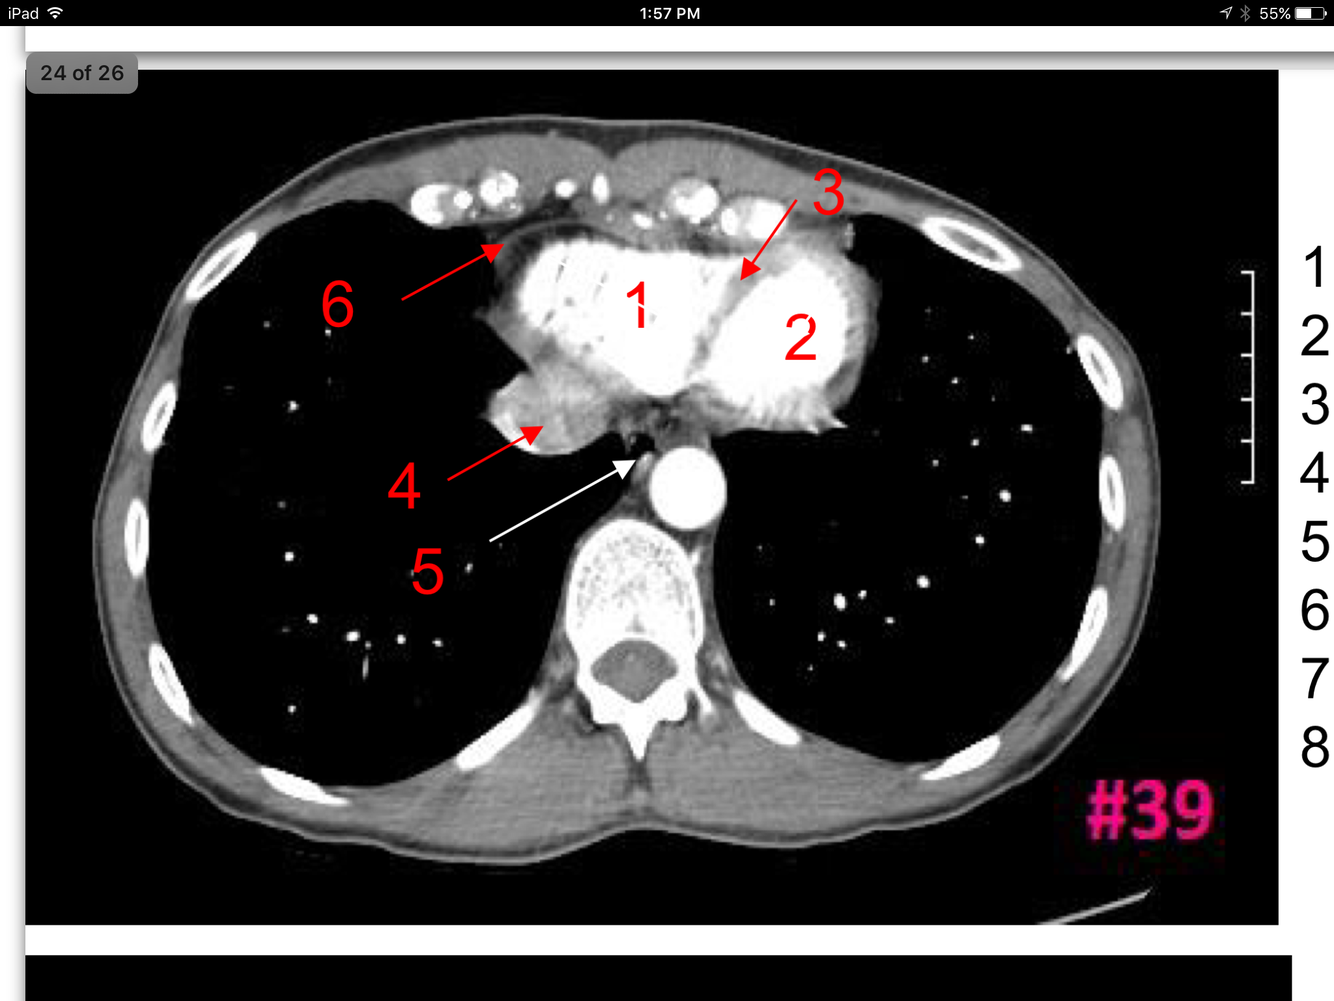

24

Q

Study These Flashcards

A

Rt ventricle

Lt ventricle

Interventricular septum

Inferior vena cava

Esophagus

Pericardium